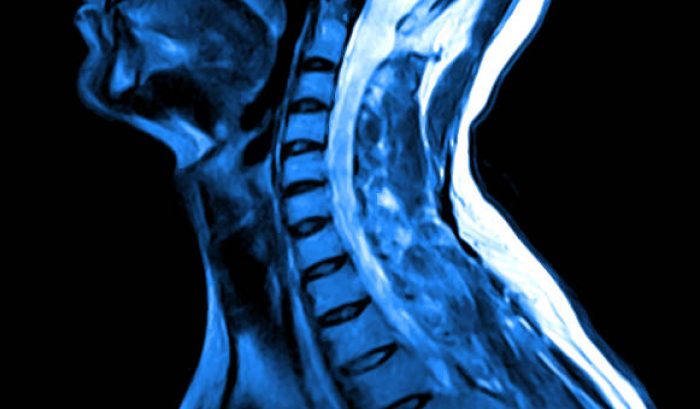

• Advanced Diagnostic Tools & Imaging Technology:

We use the latest technology to ensure accurate assessments of your ENT condition.

Our ENT, Head & Neck Surgery services offer a gateway to a world of improved health and well-being. We harness the power of advanced diagnostic tools and imaging technology to unveil the mysteries of your inner ear, nose, and throat. Our cutting-edge surgical techniques are tailored to your unique needs and provide life-changing results.